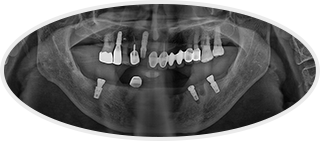

· 네비게이션 임플란트 / 임플란트 식립 2개월 후 보철물 체결 완료와 더불어 다량의 충치 크라운 치료 진행 case

• 치료 후 사진

치료 후 사진은

자세히보기에서 확인하실 수 있습니다.

+ 자세히보기